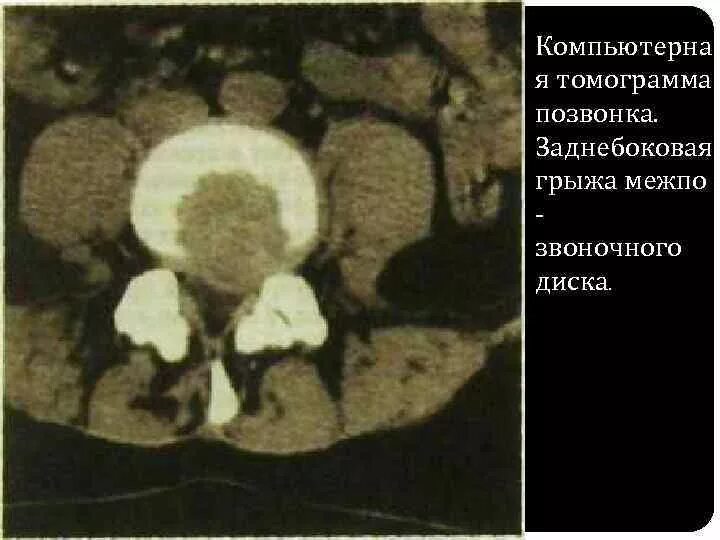

Грыжи на кт